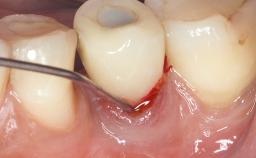

Reconstructive Treatment of a Peri-Implantitis Defect at an Implant in a Mandibular Molar Site

In this case, Mario Roccuzzo utilizes surgical bone regeneration treatment around implant 46 using a bone graft substitute and a connective tissue graft to resolve peri-implant inflammation, reduce the probing depths, and prevent further progression of disease.

A 58-year-old-male patient was referred in February 2007 for implant placement in the right mandibular molar area. Two tissue level implants were inserted at sites 44 and 46, respectively, to support a three-unit fixed dental prosthesis (FDP).